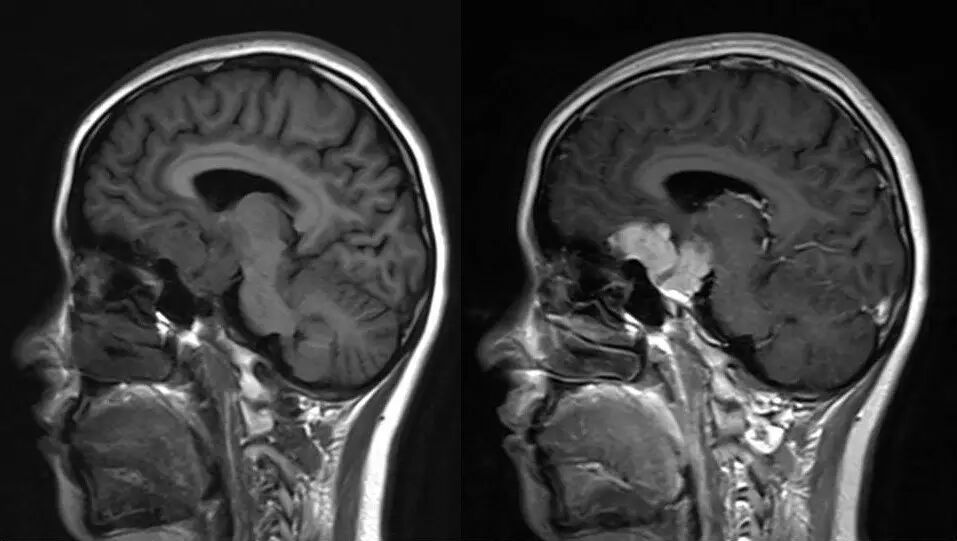

影像资料

2.MR检查显示肿瘤位于鞍区,分叶状生长,呈稍长T2、稍长T1异常信号影,边界清楚,内部信号不均匀,其内可见“微囊”状异常信号影,视交叉受压上抬,DWI呈等或略高信号影,注药后呈不均匀明显强化;

4.重点观察冠状位:病变源于垂体偏左侧,与垂体界限不清楚,肿瘤偏右侧可见垂体与肿瘤之间裂隙,造成矢状位平扫及强化后误认为正常垂体存在,从而首先除外了垂体瘤,导致误诊;

5.影像表现确定肿瘤源于垂体,部位、信号、生长方式、内部结构、骨质破坏,增强显示等均符合垂体瘤诊断。